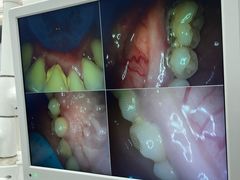

• 牙博士口腔品牌连锁(杨浦店)

• -牙博士口腔品牌连锁(杨浦店)